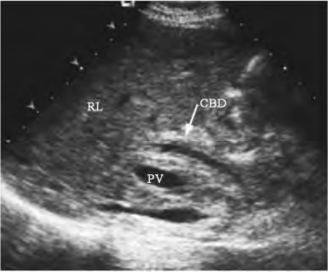

1.29第25章 胆管系统

1.29.1一、胆管系统的解剖

1.29.2二、检查方法

1.29.3三、正常超声表现